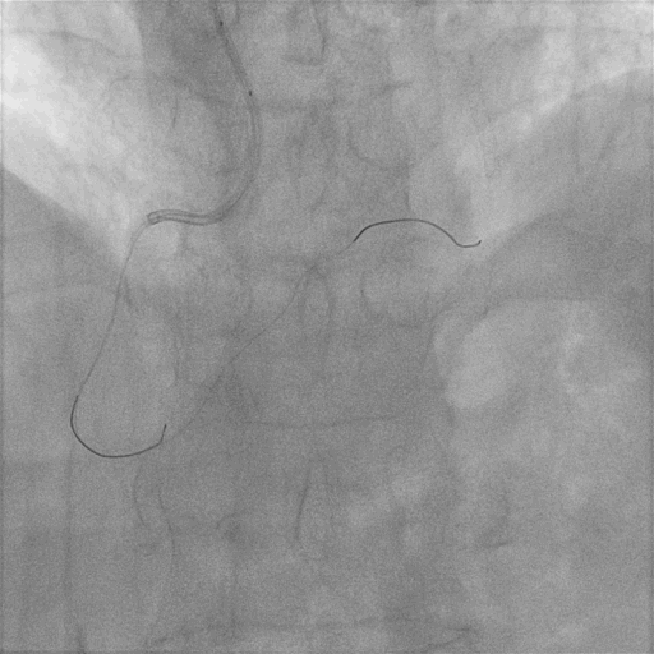

左图:AL1.0指引导管到位后,Sion导丝顺利送至右冠脉远段,迪马克2.5*15mm球囊到位困难,采用双导丝技术,球囊顺利到位后给予预扩张(10atm)。

右图:病变部位预扩后残余狭窄小于30%,病变部位未见明显夹层及撕裂,给予药物球囊鼎科2.5*20mm病变部位释放(8atm,60S)。